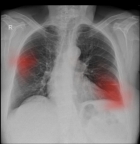

The scan above is an example of a chest x-ray processed by Enlitic, highlighting the presence of a lung nodule in the mid zone of the right lung and a linear atelectasis in the left lung. (Photo: Business Wire)

Enlitic’s first product interprets chest x-rays, triaging normal from abnormal scans, and detecting and characterizing more than 40 distinct abnormalities such as cardiomegaly, lung nodules, and pneumothorax. Chest x-rays are notoriously difficult to interpret given the image’s lack of specificity, yet they are still the most common type of radiological examination, representing an estimated 45% of all studies globally. Enlitic is working with partners around the world for the relevant approvals to deploy this product in several countries, helping radiologists to interpret chest x-rays faster, and with higher accuracy.